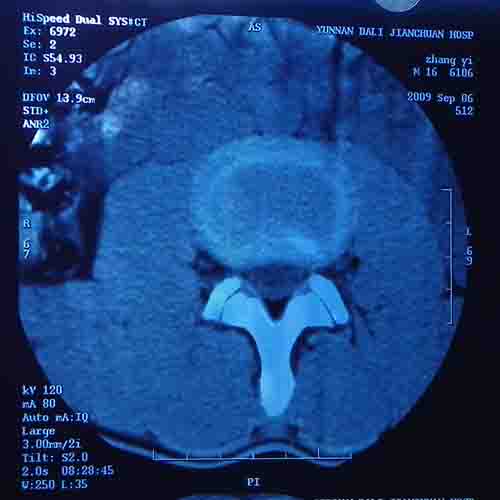

标题: CT22052:腰5/骶1椎间膨突出外,还有点异常,不知是什么东东 [打印本页]

标题: CT22052:腰5/骶1椎间膨突出外,还有点异常,不知是什么东东

腰5/骶1椎间膨突出外,还有点异常,不知是什么东东,请各位大虾帮忙看看(12骨窗最明显)

椎体后缘软骨结节